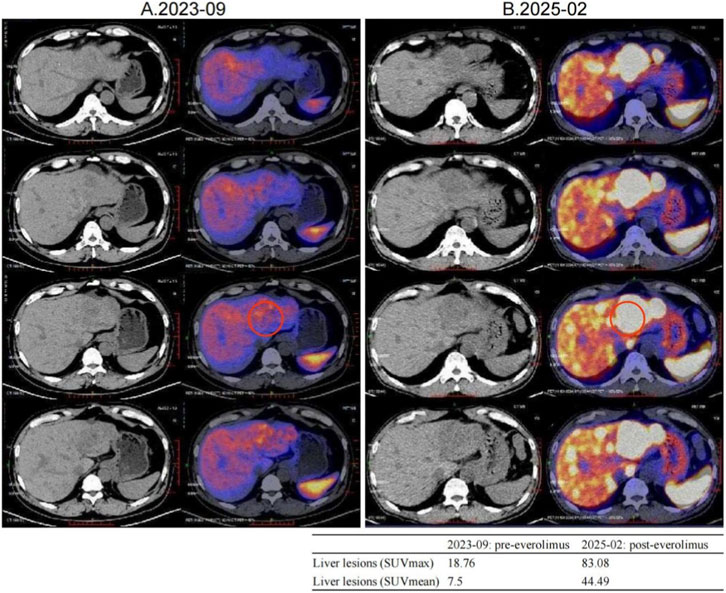

From August 2019, he received long-acting octreotide 30 mg every 4 weeks as first-line systemic therapy, combined with five sessions of transarterial chemoembolization (TACE) between 20 August 2019 and 30 October 2020. From December 2019 to February 2022, all response evaluations indicated stable disease (SD). No significant adverse events were observed; anemia improved to ∼110 g/L with iron supplementation. The August 2022 MRI showed an increased size of hepatic lesions; treatment response was assessed as progressive disease (PD), and octreotide microspheres were discontinued (Figure 1).

CT and MRI scan series show progression of liver lesions over time. Four columns labeled A.2019-07, B.2020-09, C.2022-02, and D.2022-08, each containing four images with red arrows indicating lesions. The images depict changes in liver morphology and lesion intensity.

Figure 1. Lesion changes in patients treated with first-line SSA. (A) Multiple arterial-phase hyper-enhancing nodules are observed within the liver. The largest, located in the posterior-inferior segment of the right hepatic lobe, measures approximately 2.58 cm × 1.8 cm (2019-07). (B) After 15 cycles of treatment, multiple enhanced nodules were observed in the liver in the arterial phase, which were larger in the left lateral lobe of the liver, and the enhancement was reduced in the portal phase. Treatment response evaluation: SD (2020-09). (C) At the 33rd treatment cycle, the lesion in the liver showed marginal enhancement. The larger one was located in the left lateral lobe of the liver. Treatment response evaluation: SD (2022-02). (D) During the 40-cycle treatment, the lesions in the liver increased significantly compared with before. The larger ones were in the left lateral lobe of the liver, which was significantly larger than before. Treatment response evaluation: PD (2022-08).